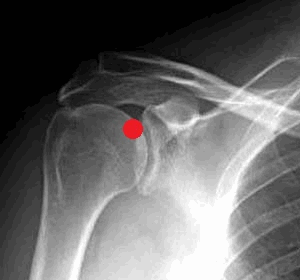

Хромота на грудную конечность из-за поражения плечевого сустава у собаки. Решения с помощью артрокопии

Хромота из-за патологии плечевого сустава может оказаться одним из самых сложных для диагностики случаев. В большей части хромота обусловлена повреждением мягких тканей. Изменения, видимые на рентгеновских снимках, неспецифичны и не позволяют поставить диагноз, за исключением случаев рассекающего остеохондрита (РОХ). Хотя для визуального исследования мягкотканных структур плеча можно использовать МРТ, артроскопия может служить как для диагностики, так и для лечения и, следовательно, является самым экономически эффективным методом в случаях хромоты у собак, обусловленной патологией плечевого сустава.

РОХ плечевого сустава

РОХ чаще всего поражает каудальную часть головки плечевой кости, клинические признаки часто развиваются в возрасте 6-12 месяцев. Заболевание может быть двусторонним, однако обычно у собаки развивается односторонняя хромота. К клиническим признакам относится периодическая хромота с сохранением опоры на конечность, болезненностью при разгибании/сгибании плеча и с атрофией плечевых мышц, из-за которой начинает выступать ость лопатки.

Рентгенография – распространенный диагностический инструмент; на снимках в медиолатеральной проекции обычно видны дефекты каудальной части головки плечевой кости. При подозрении на РОХ, если характерные изменения не видны в медиолатеральной проекции, следует сделать снимки при нагрузке, с вращением плеча наружу и вовнутрь. Пораженный участок иногда располагается не на средней линии, поэтому при развороте сустава он может лучше визуализироваться. Также выявить РОХ можно с помощью артрографии.